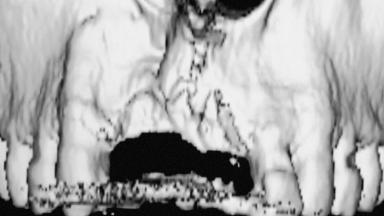

Iliac-Crest Block for Vertical and Horizontal Space Filling in the Anterior Maxilla

A 31-year-old man presented to our clinic 30 days after a motor vehicle accident in which he had suffered a dentoalveolar fracture in the anterior maxilla, including avulsion of teeth 12 and 11 and luxation of tooth 21. He was first treated on the night of the accident in a small city hospital with no oral and maxillofacial surgeon on the staff. A wired retention had been applied and the teeth repositioned to the best of the clinicians’ abilities. When he first presented to our care, the patient showed extrusion of teeth 12 and 11 associated with gingival recession due to bone loss in the anterior maxilla, and the stainless steel wires were still present.

Bone Augmentation Horizontal|Staged|Vertical

Augmentation Materials Autogenous chips|Autogenous block(s)